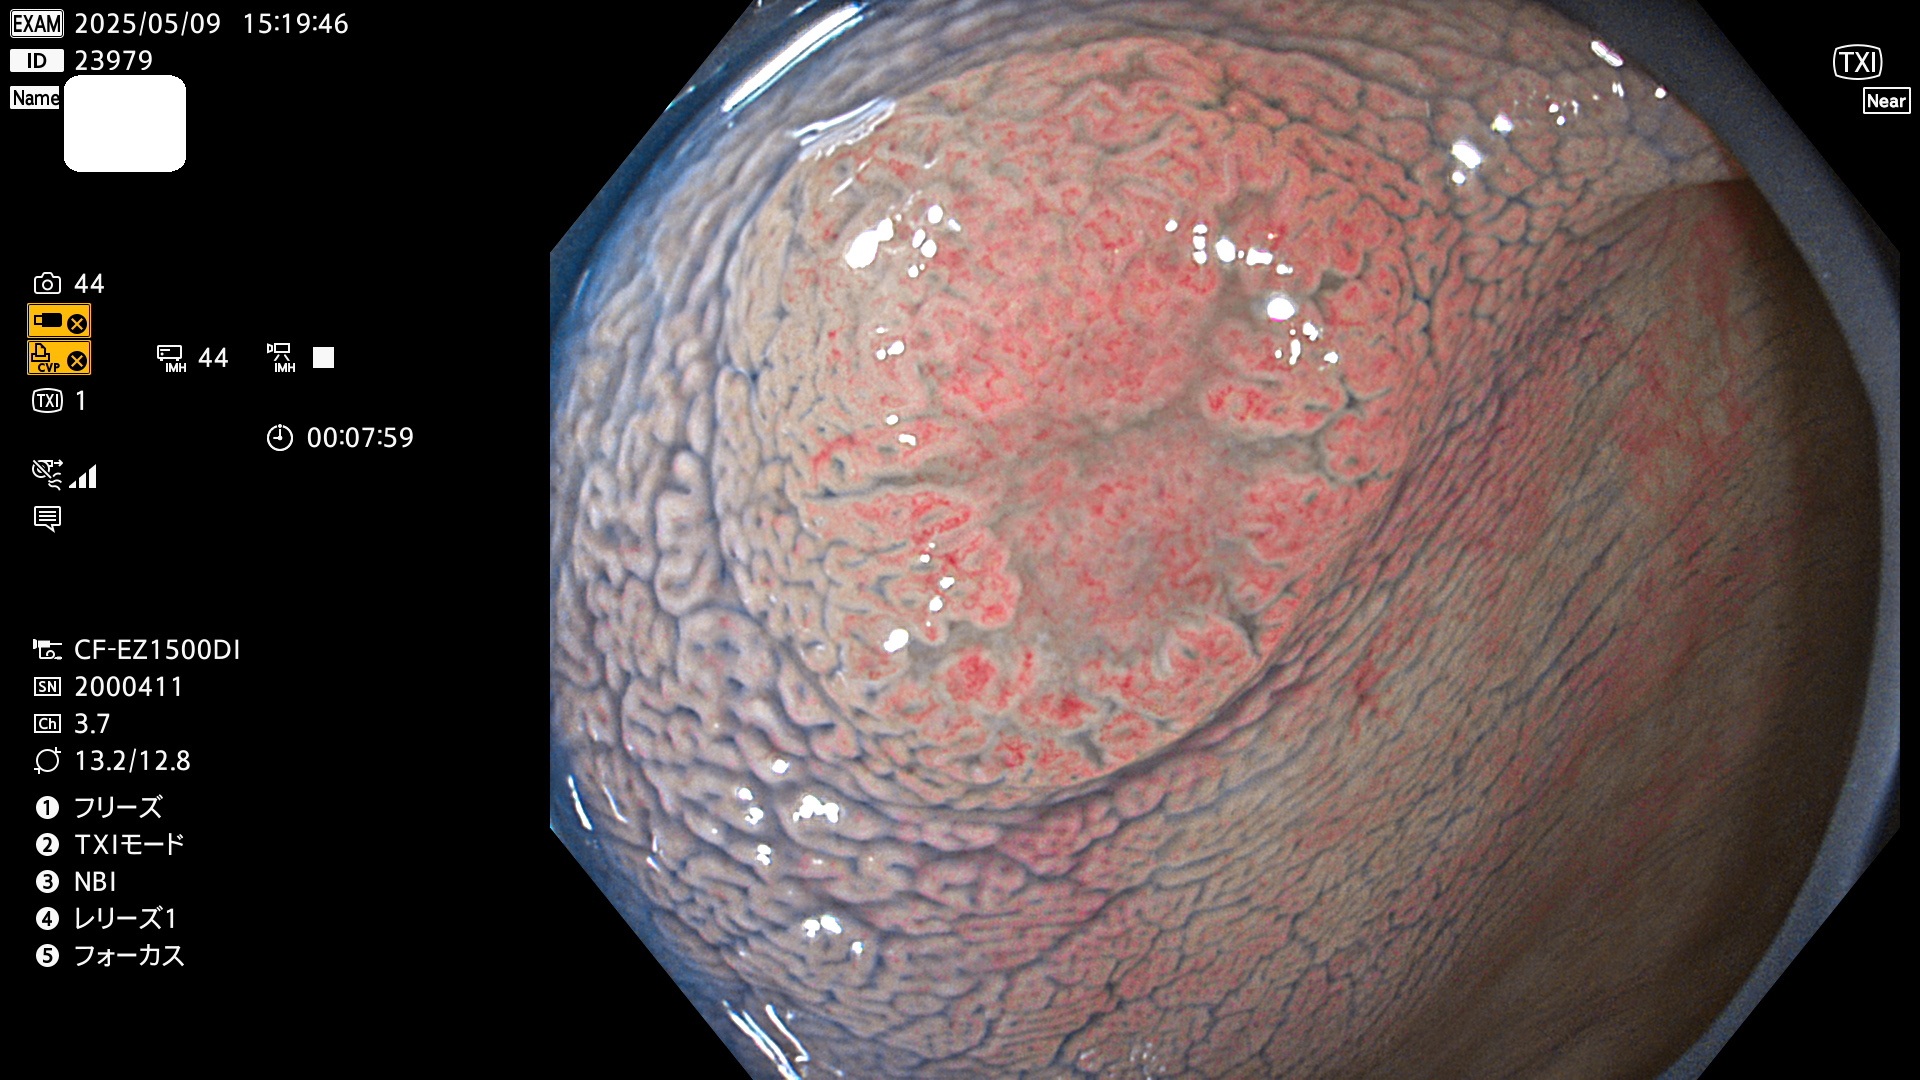

完全に平坦な物をUb、陥凹している物をUcと呼びます。Ubは認識が困難で、Ucはびらん(炎症)と紛らわしいために見落とされやすく、「内視鏡後・大腸癌」の原因になります。

抽出の対象期間 2025年5月8日〜5月11日の4日間(48件の検査)14個 (14/48=29%)